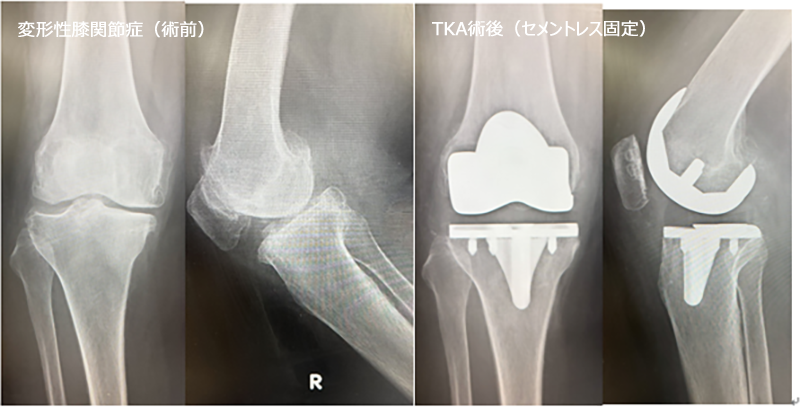

■ 人工膝関節全置換術(Total Knee Arthroplasty: TKA)

- 適応疾患: 主に変形性膝関節症(進行期)、関節リウマチによる膝関節の高度な破壊。

- 手術概要: 傷んだ膝関節の表面(大腿骨側、脛骨側、場合によっては膝蓋骨側)を削り、金属やポリエチレンでできた人工関節に置き換える手術です。関節全体を入れ替えることで、痛みを根本的に解消し、安定した歩行能力の回復を目指します。長期にわたる高い治療効果が期待できます。